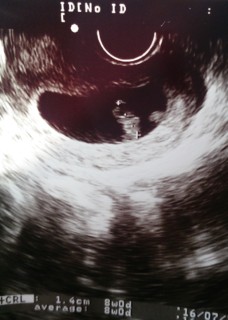

8w0d、CRL1.4cmです(*^^*)無事心拍確認できて一安心..。エコーを見た先生が、「おお~!大きくなったねぇ!赤ちゃん元気に動いてるで。」と言ってくれて、安心したのと嬉しいのとで泣けました(;_;)赤ちゃんも元気なのを見せるためか、大の字のポーズしてくれました(笑)すくすく育ってくれますように!